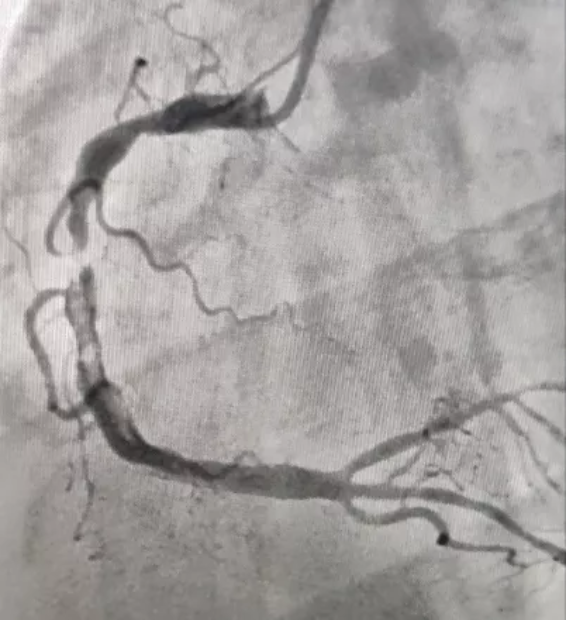

并进行支架植入术,支架植入术属于微创手术,经过精心的手术,支架在心血管内科主任邸爱群的熟练操作下下,顺利进入心血管狭窄位置,医护人员协同努力,成功为张先生的急性下壁心梗进行了血栓抽吸术和支架植入术。

支架前

支架后血运通畅